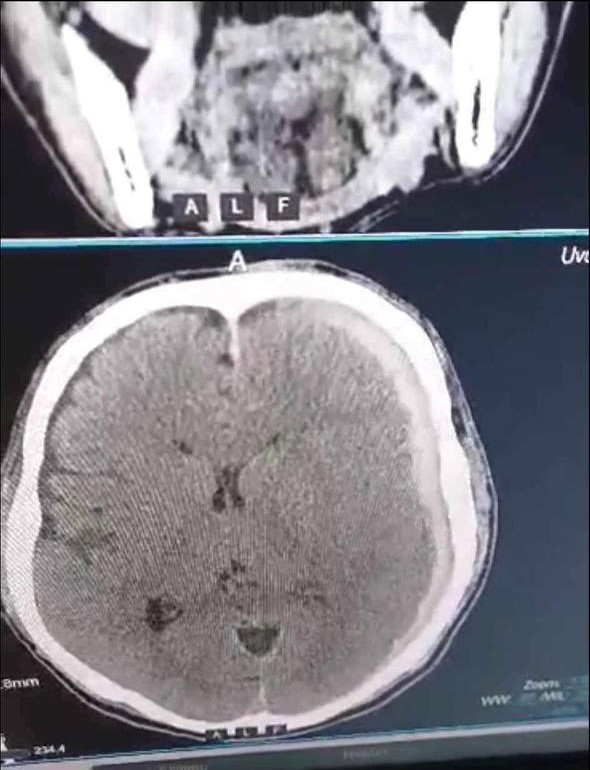

| АЛСЫН ДУУДЛАГЫН БАГ ӨВӨРХАНГАЙ АЙМАГТ ХАВСАРСАН ХҮНД ГЭМТЭЛТЭЙ ӨВЧТӨНД ЯАРАЛТАЙ МЭС ЗАСАЛ ХИЙЛЭЭ |